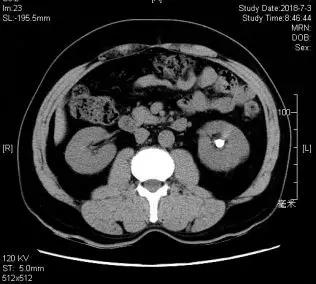

患者晁某某,因“发现左肾结石1月”入院,患者一个月前因左侧腰痛和血尿于当地医院行“输尿管软镜下碎石术”,术中因结石位于左肾下盏内,软镜视野欠佳、导致结石部分残留。术后第5天再发腰痛,后来我院就诊。我院CT显示结石位于左肾下极(图1),结石最大直径约2.0cm,外院输尿管软镜碎石失败原因,考虑为肾下盏与肾盂输尿管夹角较小,输尿管软镜存在视野盲区。陈修德主任决定对该例患者实施“超微通道经皮肾镜碎石术”。

图1 (b)CT所示左肾结石